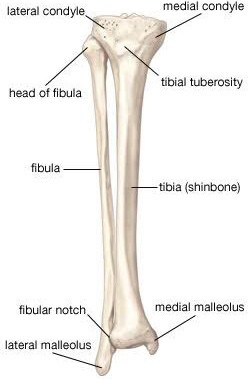

足首がかたい

足首がかたい

カイロプラクティックは背骨や骨盤だけではありません。

カイロプラクティックは背骨や骨盤だけではありません。